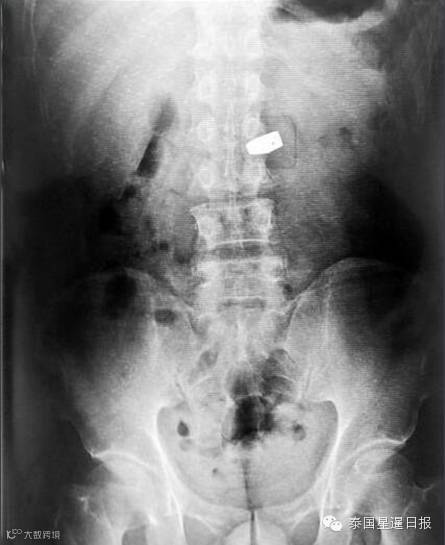

27日中午,三张配图中的另外两张的来源也被找出。第二张展现“珠宝展展会现场”的图片,来源于中国珠宝玉石首饰行业协会官方网站2009年发布的一篇文章,大标题为《中宝协组团参加第43届曼谷珠宝展》。第三张展现“X光侦测到宝石”的照片,和中文媒体2010年1月19日的一篇文章下的配图匹配度极高,该文章的大标题为《临平一中年男子一口吞下万元钻戒》。有网友怀疑,这是居心叵测人士使用假新闻诽谤侮辱中国人。

12月26日消息,一名中国女游客秦某,在泰国曼谷珠宝展上趁人不备,把一颗价值200万人民币的6克拉钻石囫囵吞下。人赃并获时,女子竟然用日语对警察道歉说“おわび申し上げます”(我对此非常抱歉)。事后,警察在检查护照时发现,该女子确系中国人。警方通过X光,找到位于其大肠中的钻石,并让医生使用肠镜等器械将钻石从该女子的肠中取出。